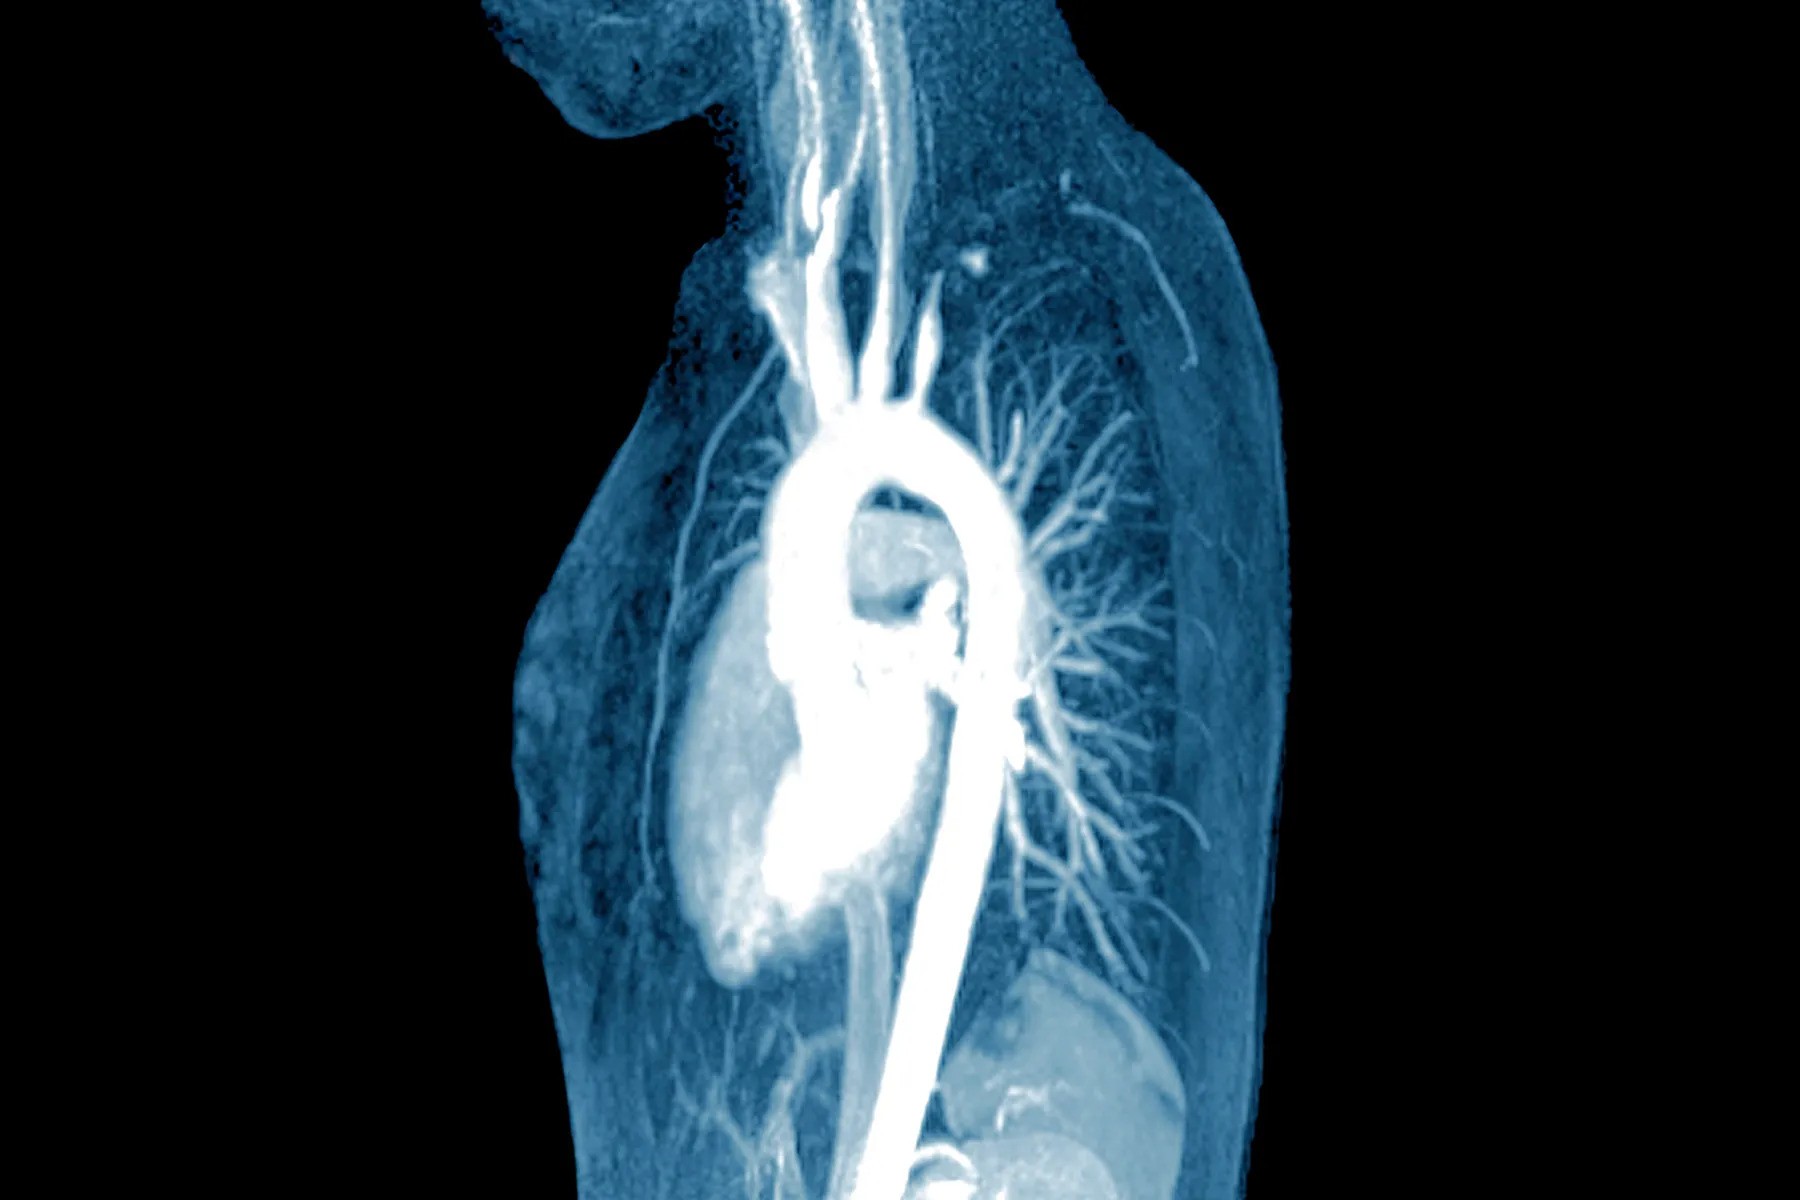

Αρτηρίτιδα Takayasu. Μη ειδική αορτίτιδα με κακή πρόγνωση που επηρεάζει, κυρίως, την αορτή και τους κλάδους της και τις πνευμονικές αρτηρίες

H αρτηρίτιδα Takayasu, ICD-10 M31.4 ή σύνδρομο Takayasu ή νόσος Takayasu ή σύνδρομο του αορτικού τόξου ή μη ειδική αορτοαρτηρίτιδα ή άσφυγμη ασθένεια ή άσφυγμη νόσος ή αρτηρίτιδα των νεαρών γυναικών ή ανάστροφη ισθμική στένωση ή σύνδρομο Mertorell ή βραχιονοκεφαλική ισχαιμία είναι μια μορφή κοκκιωματώδους αγγειίτιδας των μεγάλων αγγείων με μαζική ίνωση του έσω χιτώνα και αγγειακή στένωση που επηρεάζει συχνά νέους ή μεσήλικες γυναίκες ασιατικής καταγωγής.

Επηρεάζει, κυρίως, την αορτή (το κύριο αιμοφόρο αγγείο της καρδιάς) και τους κλάδους της, καθώς και τις πνευμονικές αρτηρίες. Οι γυναίκες είναι περίπου 8-9 φορές πιο πιθανό να επηρεαστούν από τους άνδρες. Οι ασθενείς, συχνά, παρατηρούν τα συμπτώματα της νόσου μεταξύ 15 και 30 ετών.

Αν και η αιτιολογία της είναι άγνωστη, η κατάσταση χαρακτηρίζεται από τμηματική και αποσπασματική κοκκιωματώδη φλεγμονή της αορτής και των μεγάλων κλάδων της. Αυτή η φλεγμονή οδηγεί σε αρτηριακή στένωση, θρόμβωση και ανευρύσματα. Υπάρχει, επίσης, ακανόνιστη ίνωση των αιμοφόρων αγγείων που οφείλεται σε χρόνια αγγειίτιδα, οδηγώντας μερικές φορές σε μαζική ίνωση του έσω χιτώνα (η ίνωση του εσωτερικού τμήματος των αιμοφόρων αγγείων). Η ευδιάκριτη στένωση οφείλεται σε φλεγμονή, κοκκίωμα και η ίνωση φαίνεται σε αρτηριακή μελέτες, όπως η μαγνητική αγγειογραφία, η αξονική τομογραφία αγγειογραφία ή η ψηφιακή αγγειογραφία.